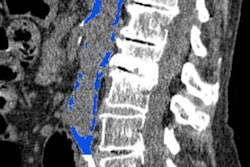

To see if more insurance-covered options would increase colorectal cancer screening, the researchers sought to compare overall screening rates in patients with and without insurance coverage for CTC colorectal cancer screening. They retrospectively reviewed longitudinal electronic health record data for 33,177 patients from 2005 through 2010 at a large multispecialty physician group. All patients were younger than 65 and were eligible and due for colorectal cancer screening.

- CTC: 1,945 screening tests (11%)